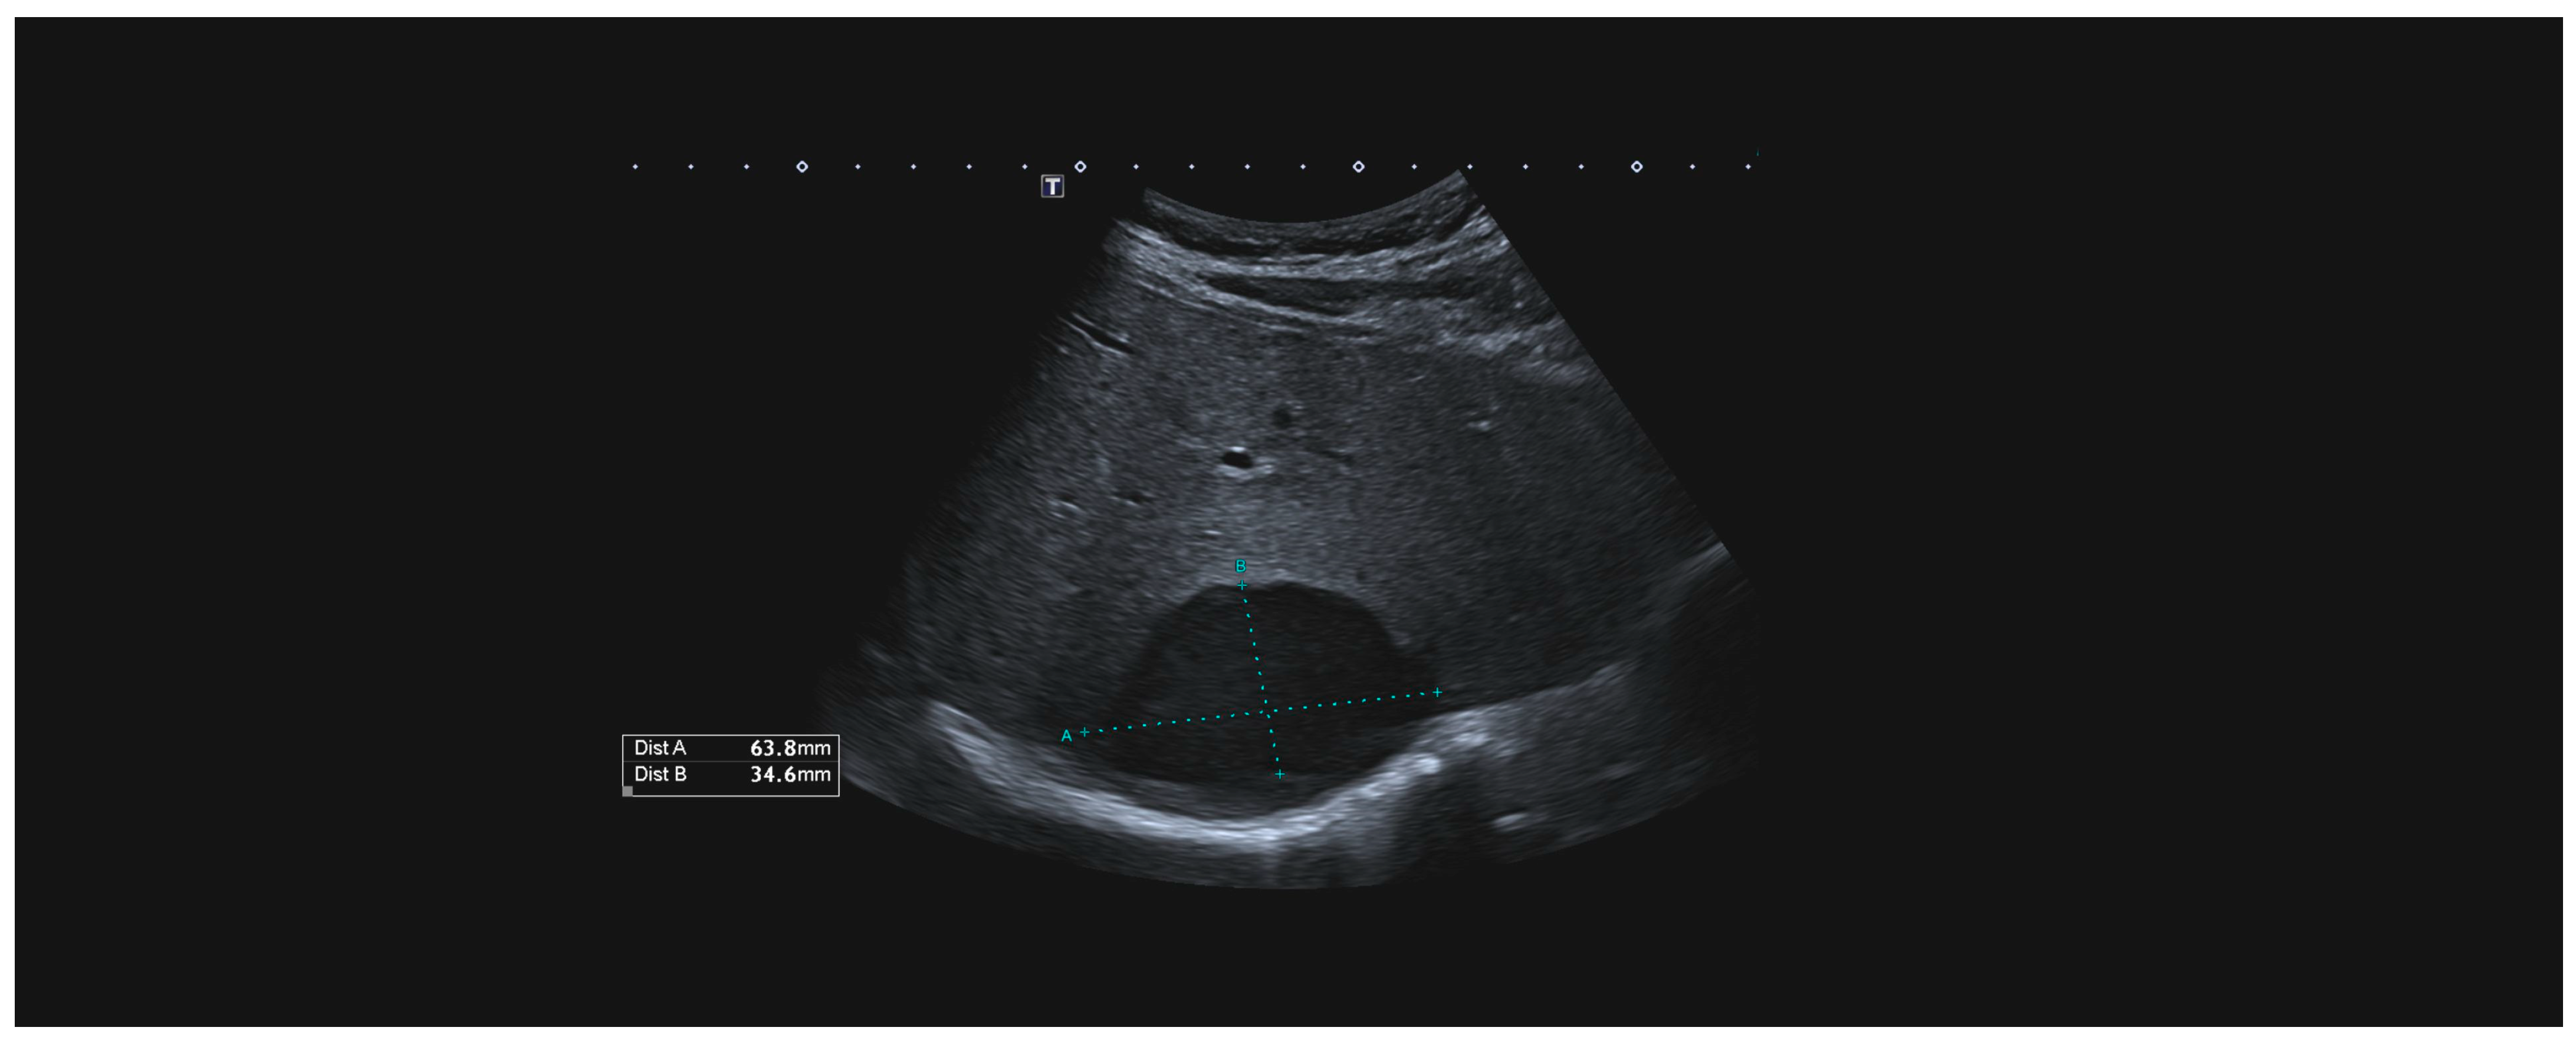

The only patient who received conservative treatment was stable after admission, and an MRI of the heart showed liver injury. Intraparenchymal haematoma of the liver without active bleeding was confirmed by CT scans (Figure 3). The haematoma was repeatedly re-evaluated by ultrasound (Figure 4), and the patient was later discharged.

Figure 4.

US examination of the intraparenchymal haematoma.